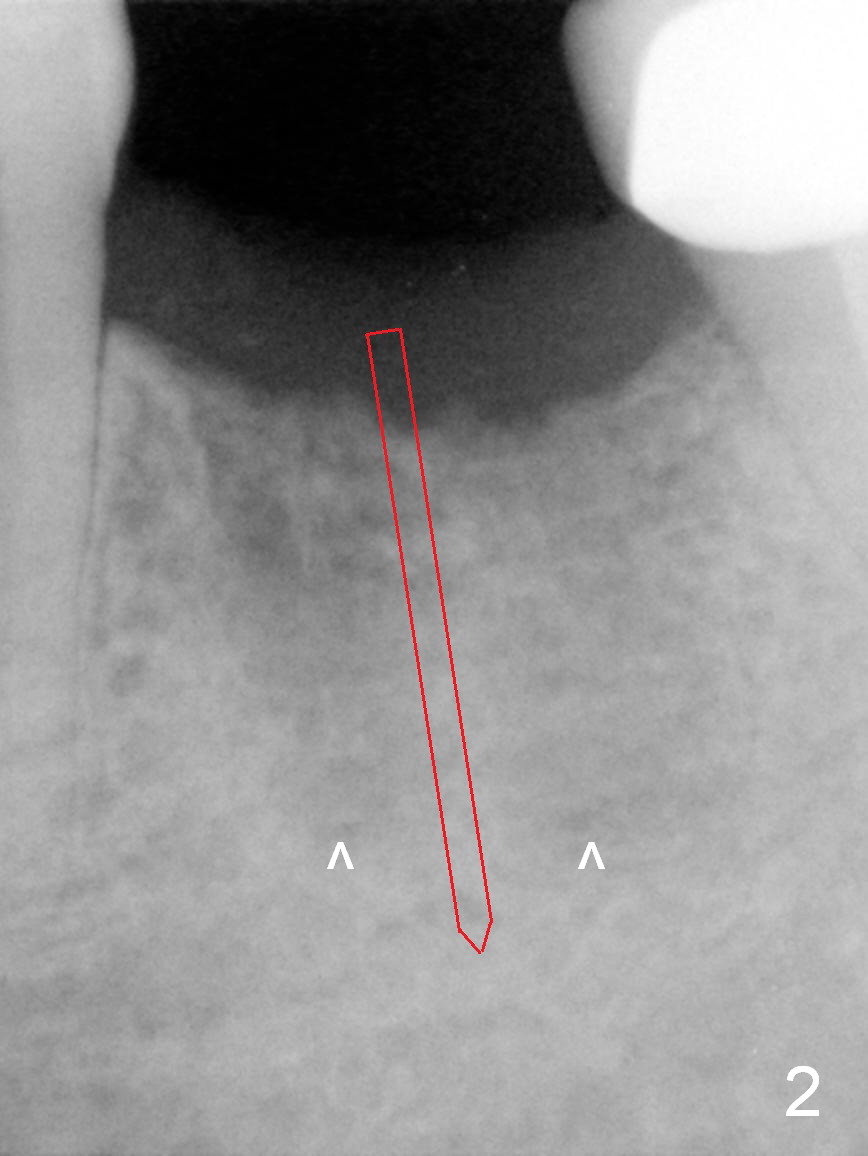

A 68-year-old man had the tooth #19 extracted more than 6 months ago (Fig.1). When his wife has had an immediate implant placed, he decides to have his implant placed. After incision, use the 5 mm implant positioner to check the width of the crestal bone. If it is less than 6 mm, the implant length will be most likely 14 mm. Clinical exam has revealed moderate ridge atrophy. Anyway, the initial osteotomy is 12 mm. It should pass the apices of the mesial (M) and distal (D) sockets (Fig.2 ^) in the middle of the septum (as compared to Fig.1 S). If there is enough safety margin, the osteotomy depth will be set at 14 mm (Fig.3 (red dashed line: the superior border of the Inferior Alveolar Canal)). There is no indication for intraop localized use of antibiotic.